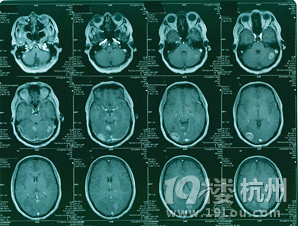

颅内多发转移瘤射波刀怎么治-网上问医-杭州1

300x379 - 32KB - JPEG

300x370 - 31KB - JPEG

300x226 - 36KB - JPEG

300x204 - 28KB - JPEG